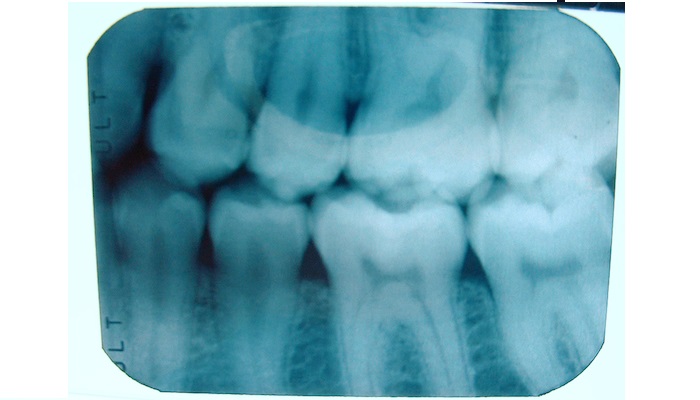

Our dental professionals have many years experience and regularly attend updated courses enabling us to offer all the latest techniques and materials.

Featured Proceedures